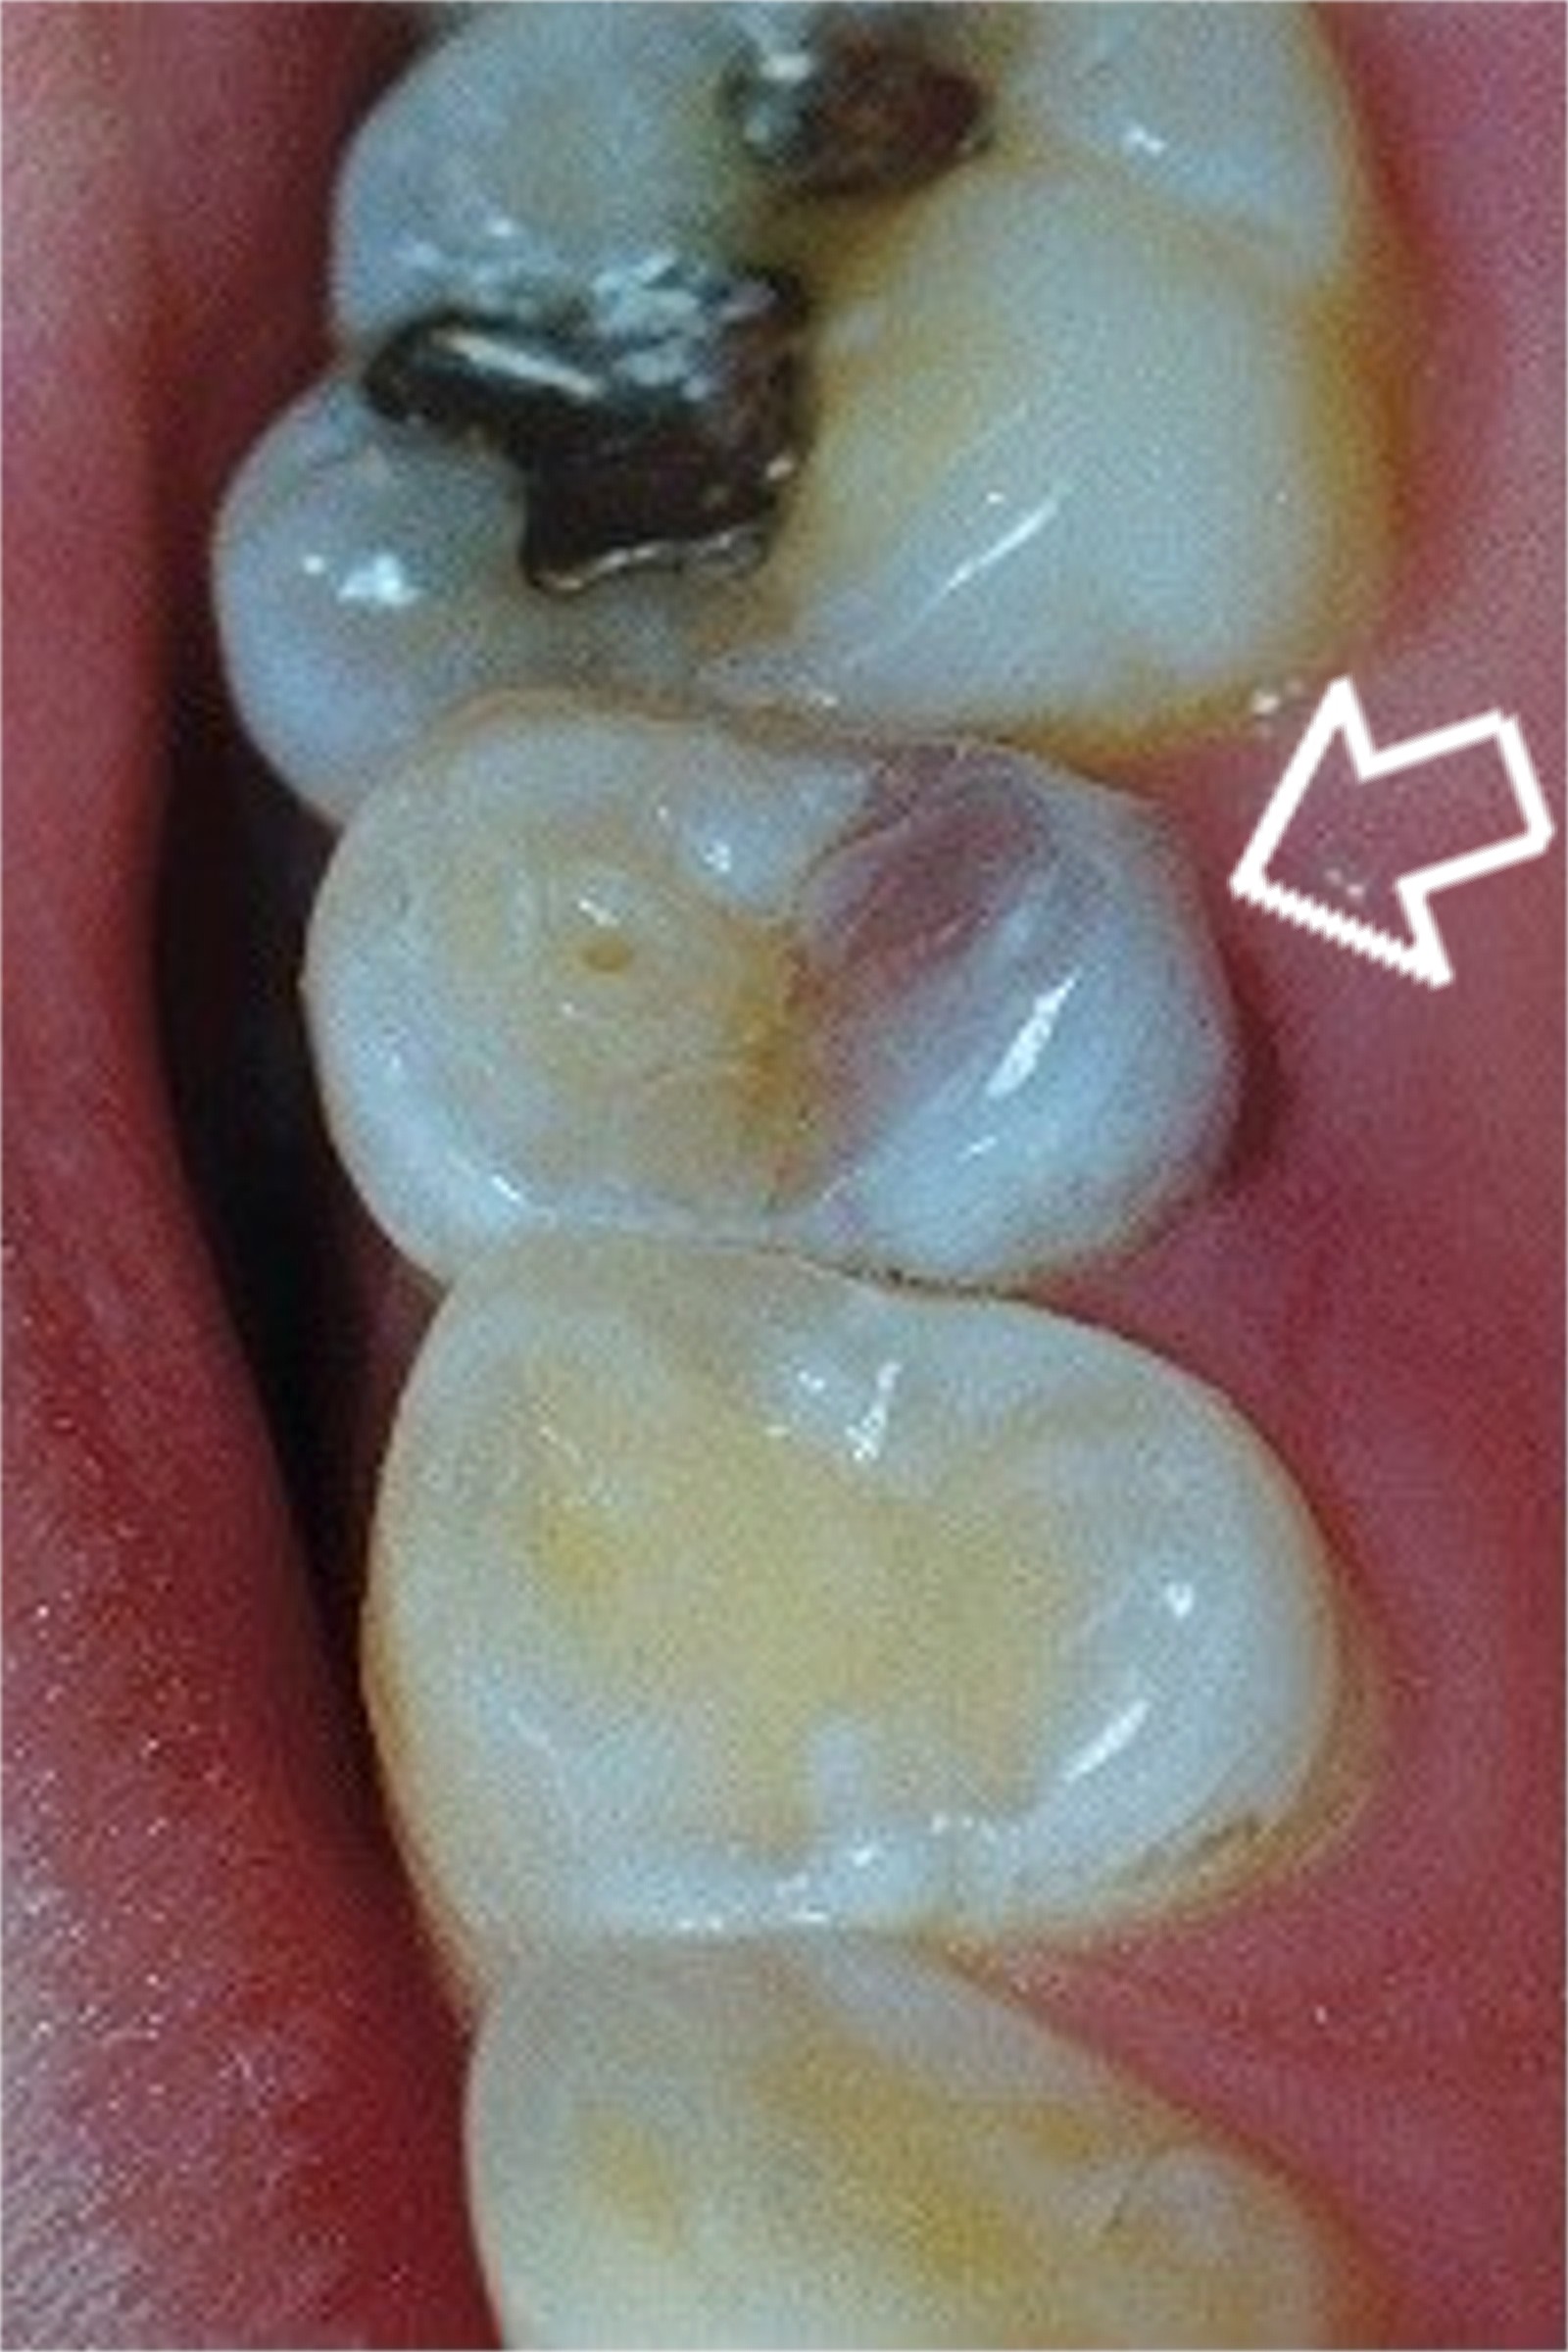

Necrotic Tooth - a tooth which has died

Though many teeth which die do NOT discolore, the dark purple area of this premolar indicates that the pulp of the tooth has died, likely due to a cavity or other trauma.  Such a tooth needs root canal or other treatment in a timely manner to prevent extensive infection and abscess.   Once a tooth has died, it tends to become brittle and will eventually break down without proper treatment from your dentist.  Since the tooth has died, it may not feel sensitive to the patient and is often ignored.  As a dentist, I routinely see patients who have broken off the entire crown of a necrotic tooth!  Though the tooth may still be saved (ie- see our Cosmetic Dentistry page) after it has broken off, it may also need to be extracted.

dental darkened tooth photo